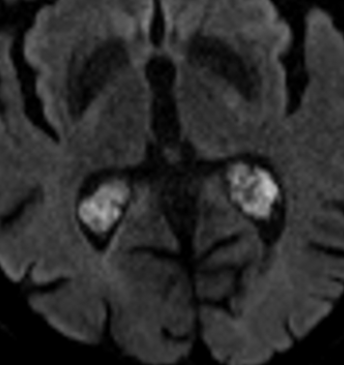

- Lésions Kystiques à Paroi Calcifiées

- Peuvent restreindre la Diff